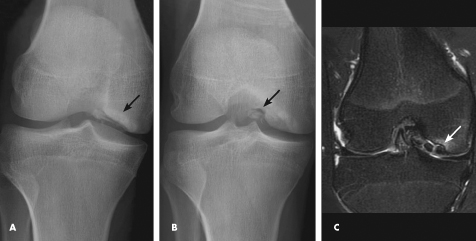

Anteroposterior and tunnel views of the right knee are shown.

Discussion: The radiographs show an osteochondral defect in the lateral aspect of the medial femoral condyle with intraarticular loose bodies (A and B). MRI of the knee, to delineate the extent of the lesion, shows an unstable, stage 4 osteochondral defect that involves the distal medial femoral condyle with at least 3 intra-articular loose bodies (C). In addition, there is small knee joint effusion with changes of mild synovitis.